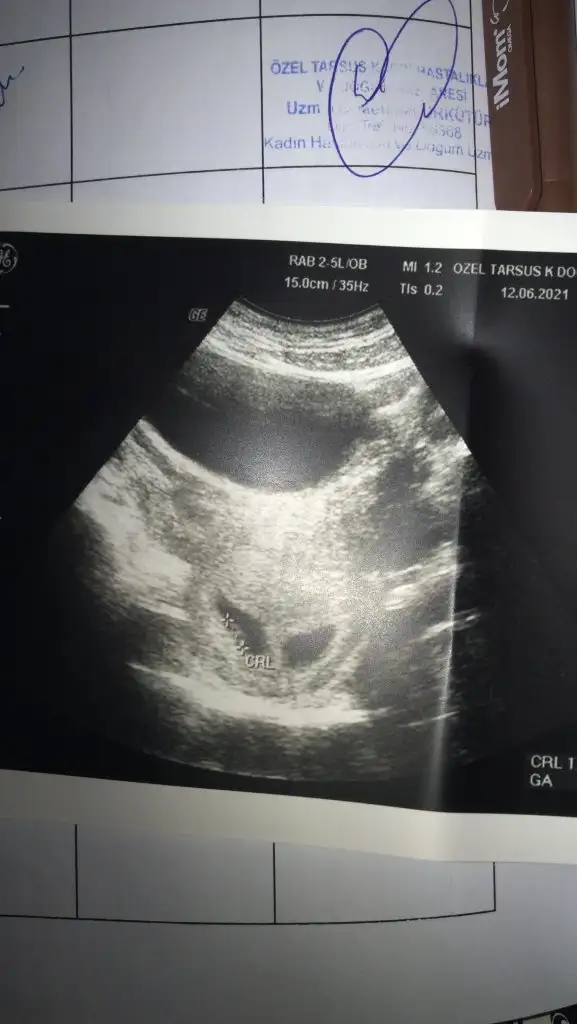

Bende karindan ultrasyon yorum yapabilirmissiniz

Eklentiler

• IMG-20210526-WA0004.webp

23,6 KB · Görüntüleme: 599